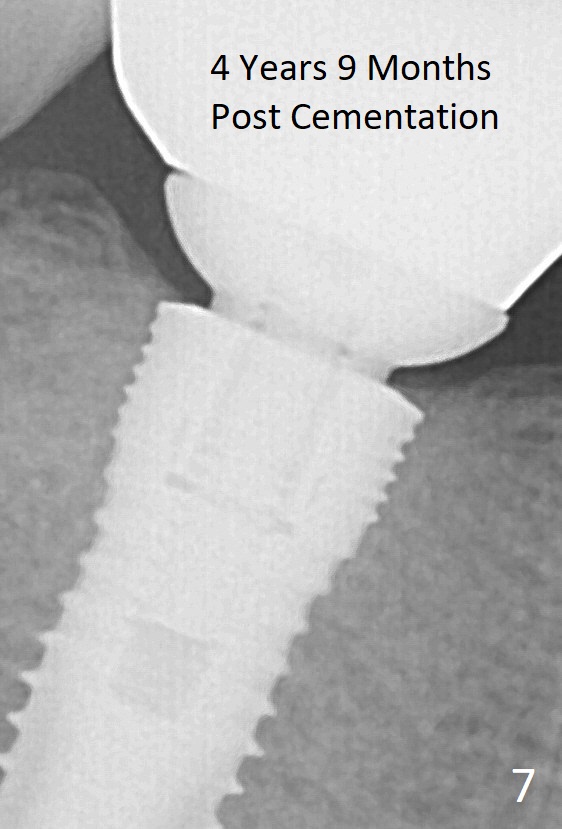

Fig.1 and 2 show a 5.3x12 mm bone level implant immediately and 6.5 months post placement, respectively. The gingiva looks normal at the site of #30 6.5 months postop (Fig.3). A small incision is made for uncover and a large healing abutment (9.2 mm) is placed (Fig.4 (buccal view), 5 (lingual)). It appears that an interdental papilla forms instantaneously (Fig.4 *). The wound is covered by periodontal dressing. To reduce the chance of post-implant infection, several things should be done. First. the extraction socket should be thoroughly debrided, copiously irrigated and soaked with an antibiotic. Second, any gaps remaining after implant placement should be filled with bone graft, which could be mixed with an antibiotic. Third, the wound should be closed as tight as possible. Either the implant is buried (bone level) or a short abutment over a tissue-level implant or healing abutment over a bone level implant is placed so that periodontal dressing can be applied around the wound. Fourth, an antibiotic is taken pre- and post-op. There is no bone loss around the implant 21 months post cementation (Fig.6) or 4 years 9 months post cementation (Fig.7). Return to Professionals Implant Failure Xin Wei, DDS, PhD, MS 1st edition 07/26/2014, last revision 06/13/2019